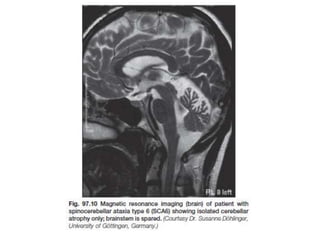

SCA-6

• Imaging reveals isolated cerebellar atrophy with no

brainstem involvement

SCA-6 • SCA6 isthe second most common subtype of SCAs following SCA3 • It has relatively pure cerebellar signs and occasional minor pyramidal signs • It has a slow progression with a normal lifespan. • Because of the late onset, SCA6 often may present with no positive family history and No anticipation • Imaging reveals isolated cerebellar atrophy with no brainstem involvement